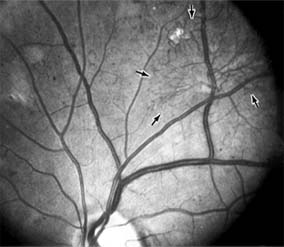

The visual and electrophysiologic dysfunctions associated with diabetes probably result from the local vascular abnormalities and the systemic metabolic effects of the disease to which the retina is subjected. A characteristic blue-yellow color vision abnormality develops, and hue discrimination may be impaired. Contrast sensitivity may be reduced in patients, even in the presence of normal visual acuity. Visual field testing may show relative scotomas corresponding to areas of retinal edema and nonperfusion, and abnormalities in dark adaptation have also been described. Electroretinographic abnormalities bear a relationship to the severity of retinopathy and may aid in predicting progression of retinopathy. Fluorescein angiography is invaluable in defining the microvascular abnormalities of diabetic retinopathy (Figures 10-21 and 10-22). Large filling defects of capillary beds-"capillary nonperfusion"-show the extent of retinal ischemia (Figure 10-23) and are usually most prominent in the midperiphery. The fluorescein leakage associated with retinal edema may assume the petaloid configuration of cystoid macular edema or may be diffuse. Other fluorescein abnormalities include vascular loops and intraretinal shunts. The focus of treatment in patients with nonproliferative diabetic retinopathy and no macular edema is treatment of hyperglycemia and intercurrent systemic disease. A controlled clinical trial has shown that aldose reductase inhibitor therapy does not prevent progression of diabetic retinopathy. Focal argon laser treatment of discrete points of retinal leakage in patients with clinically significant macular edema, principally defined as thickening of the retina at or within 500 0x0003bcm of the center of the macula, reduces the risk of visual loss and increases the likelihood of visual improvement (see Chapter 24). Eyes with diabetic macular edema that is not clinically significant should usually be monitored closely without laser treatment. Since macular edema may be present with little or no change in visual acuity and requires slitlamp biomicroscopic retinal examination for full evaluation, primary health care providers should recognize the importance of prompt and early referral of diabetic patients to the ophthalmologist.

Figure 10-21: Fluorescein angiogram in nonproliferative diabetic retinopathy shows microaneurysms (arrow) and perifoveal retinal vascular changes.

Figure 10-22: Late phase fluorescein angiogram shows hyperfluorescence typical of noncystoid diabetic macular edema.

Figure 10-23: Fluorescein angiogram shows hypofluorescence from capillary drop-out (arrows) typical of ischemic diabetic maculopathy.